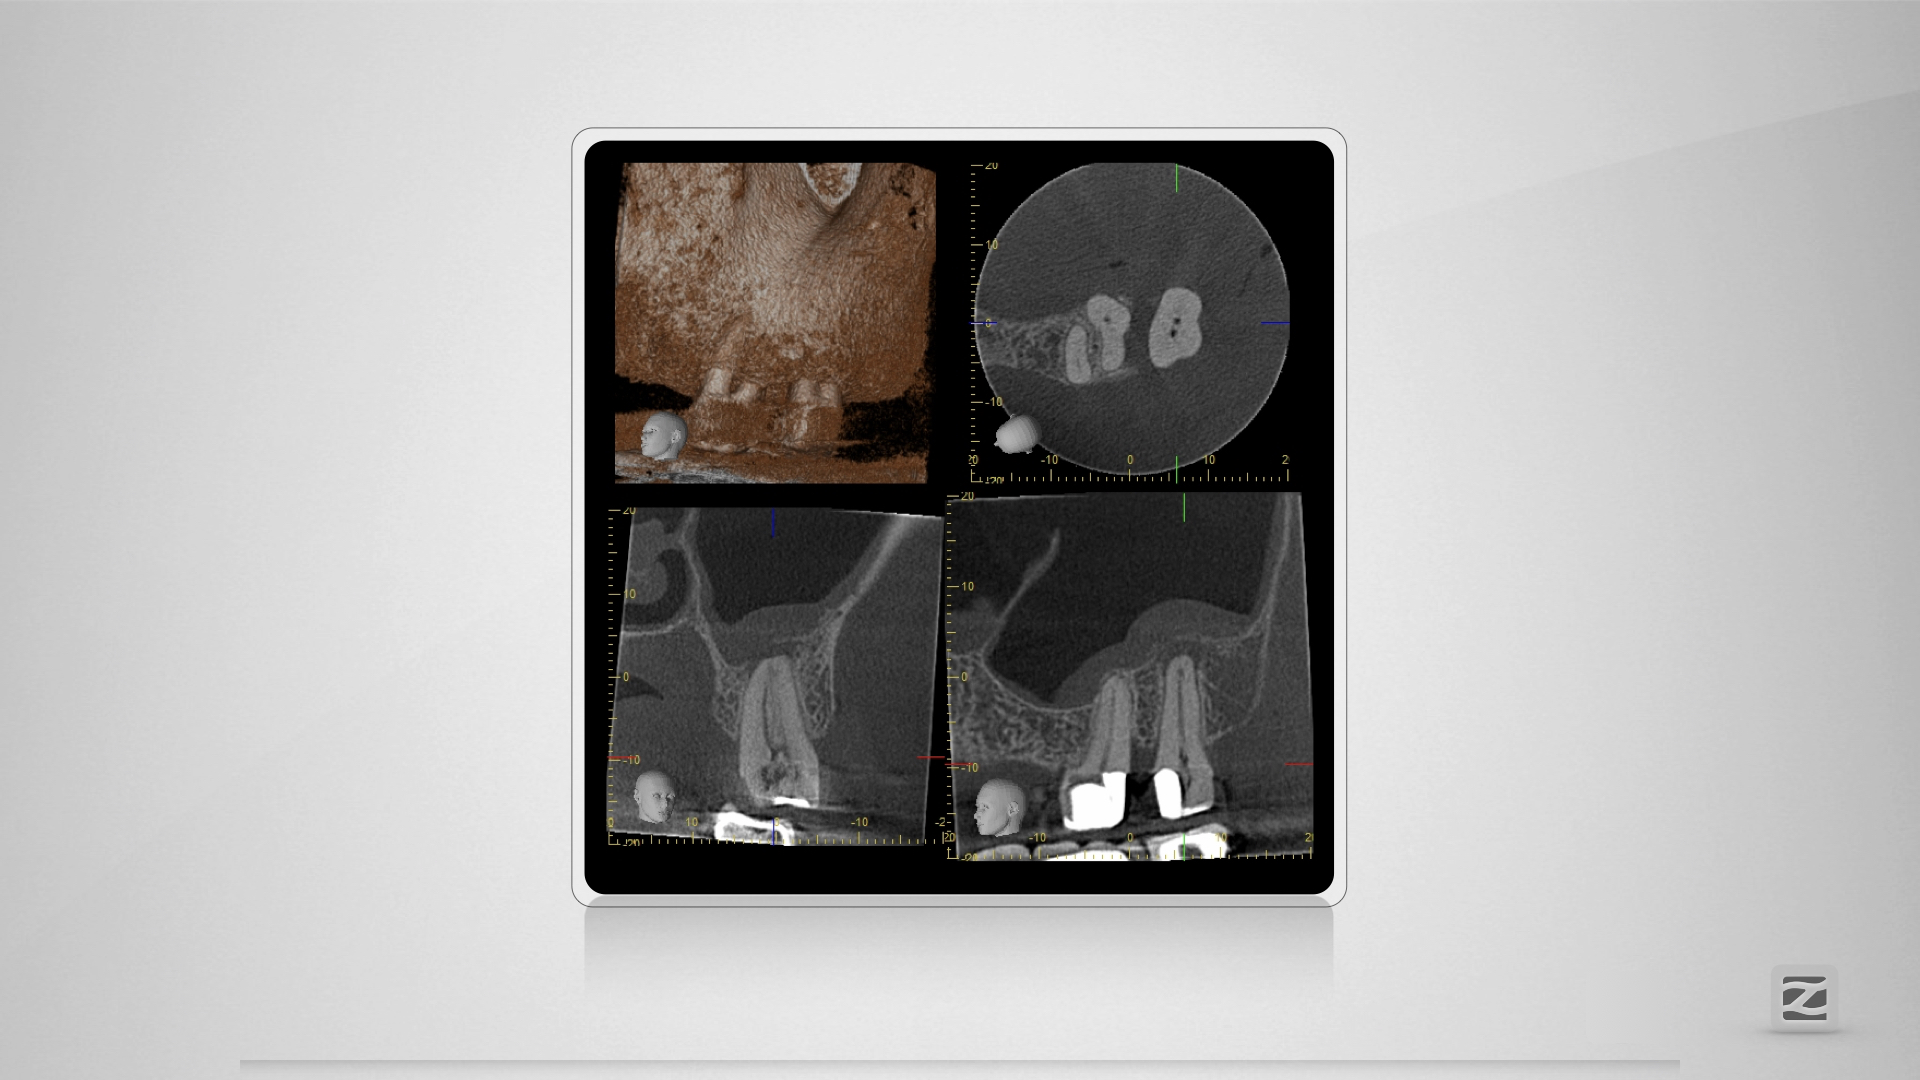

27D.002

Großer Dentikel, tiefer Split.